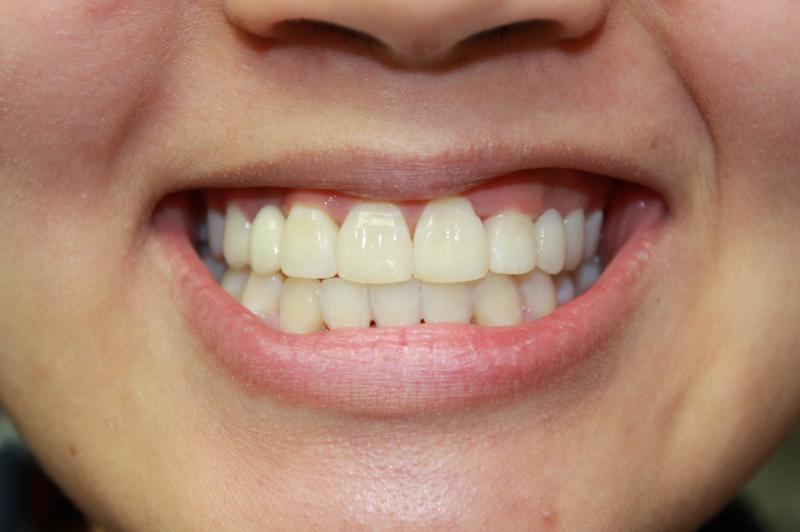

Trang H.

Invisalign Case

INVISALIGN - 13 months, 1 lower tooth removal, 1 series of aligners to align teeth and create the proper amount of space for 2 cantilever bridge to replace congenitally missing cuspids. COSMETIC DENTISTRY - 2 porcelain cantilever bridges and cosmetic bonding to reshape incisors and close gingival spaces. TOTAL TREATMENT TIME, 15 months

Cosmetic Dentistry, Mid-line Asymetry, Missing Teeth, Severe Crowding